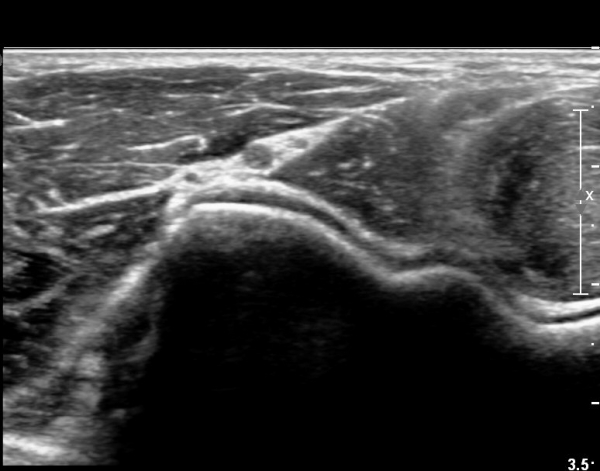

ŽÃËÀÚ¸¦ Á¶±Ý ´õ À̵¿ÇÏ´Ï Èİñ°£ ½Å°æÀÇ ºÎÁ¾ÀÌ ´Ù½Ã °üÂûµÈ´Ù(»çÁø 3).